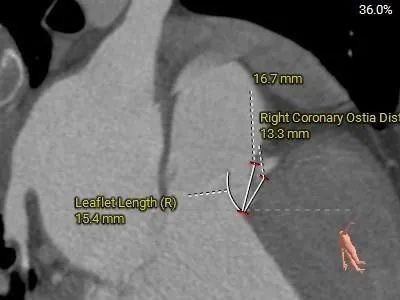

冠脉测量

左、右冠开口高度可,切线位测量,左、右窦瓣叶长于冠脉开口下缘

• 左、右冠开口高度可,切线位测量,左、右窦瓣叶长于冠脉开口下缘,结合瓦氏窦、STJ内径综合预估,冠脉阻塞风险适中。